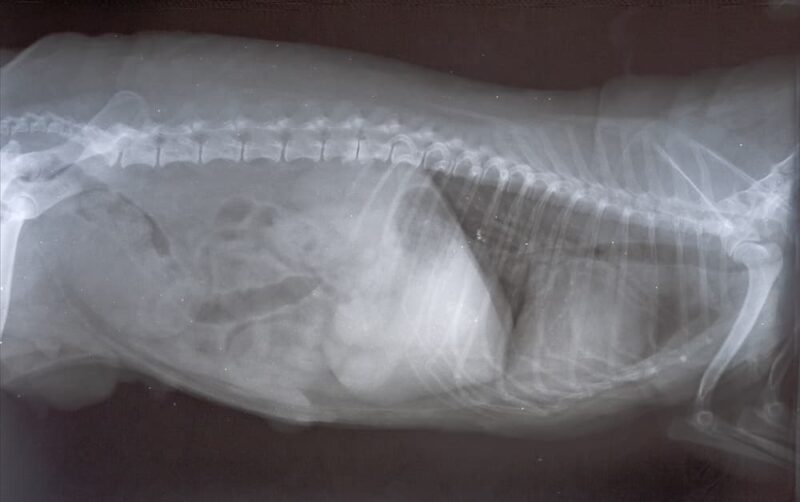

Breast Cancer in Dogs Diagnosis, Treatment & Prognosis Types Of Breast Cancer In Dogs Most mammary tumors tumors are carcinomas that begin as a lump on the abdomen near the dog's. The most common type of mammary cancer in dogs is known as mammary carcinomas (malignant) or mammary adenomas (benign). Mammary tumors are common in dogs and are the most common type of neoplasia in sexually intact females. Breast cancer is relatively common in. Types Of Breast Cancer In Dogs.